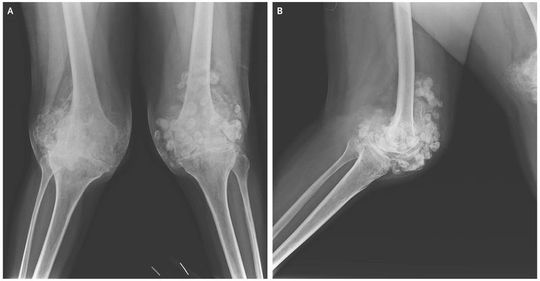

A 46-year-old woman presented to the rheumatology clinic with a 3-month history of walking difficulty due to worsening knee pain. She had received a diagnosis of rheumatoid arthritis 12 years earlier but had received treatment inconsistently, with frequent changes between prescribed medical therapies and complementary medicine practices. On physical examination, she had nodular swelling and outward bowing of both knees. She had limited range of motion in her left shoulder and in both wrists and both knees. The number of swollen and tender joints, the disease activity score, and elevated C-reactive protein level were consistent with active rheumatoid arthritis. Radiographs of the knees showed multiple calcified loose bodies and narrowing of the joint space (Panel A, anteroposterior view; Panel B, lateral view). These findings were consistent with synovial chondromatosis, a disorder of the synovium that is characterized by the development of loose cartilaginous bodies. For treatment of the rheumatoid arthritis flare, she was given methotrexate and folic acid with short-term glucocorticoids. The treatment of synovial chondromatosis can include surgery; however, the patient declined surgical evaluation. At follow-up 3 months later, her disease activity score for rheumatoid arthritis had decreased, and she had moderate reduction in her knee pain and enhanced mobility with the use of a walker.